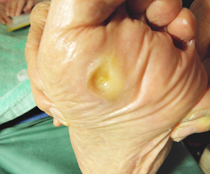

巻き爪、タコ、魚の目等があると症例に示すように、様々な症状を呈します。

早いうちに処置をして快適な生活を心がけましょう。